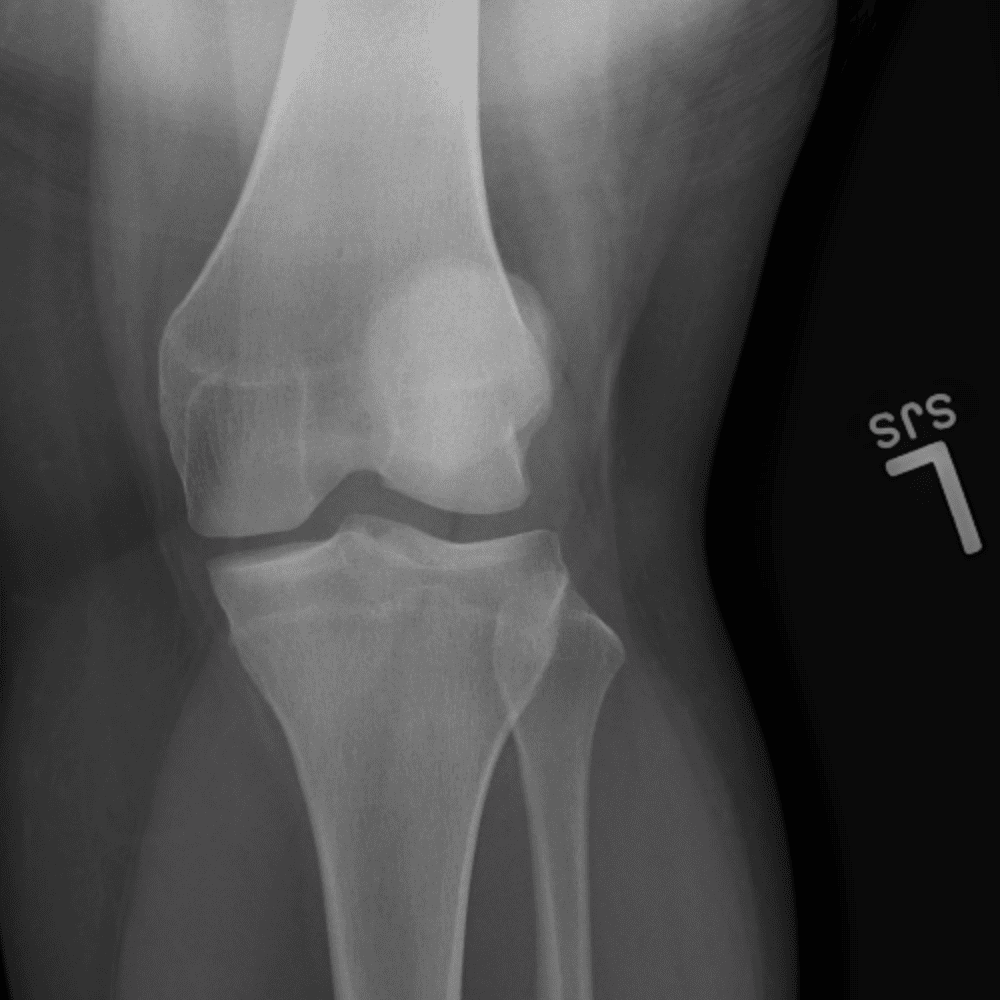

Simula o plantão incluindo casos sutis ou difíceis e alguns normais.